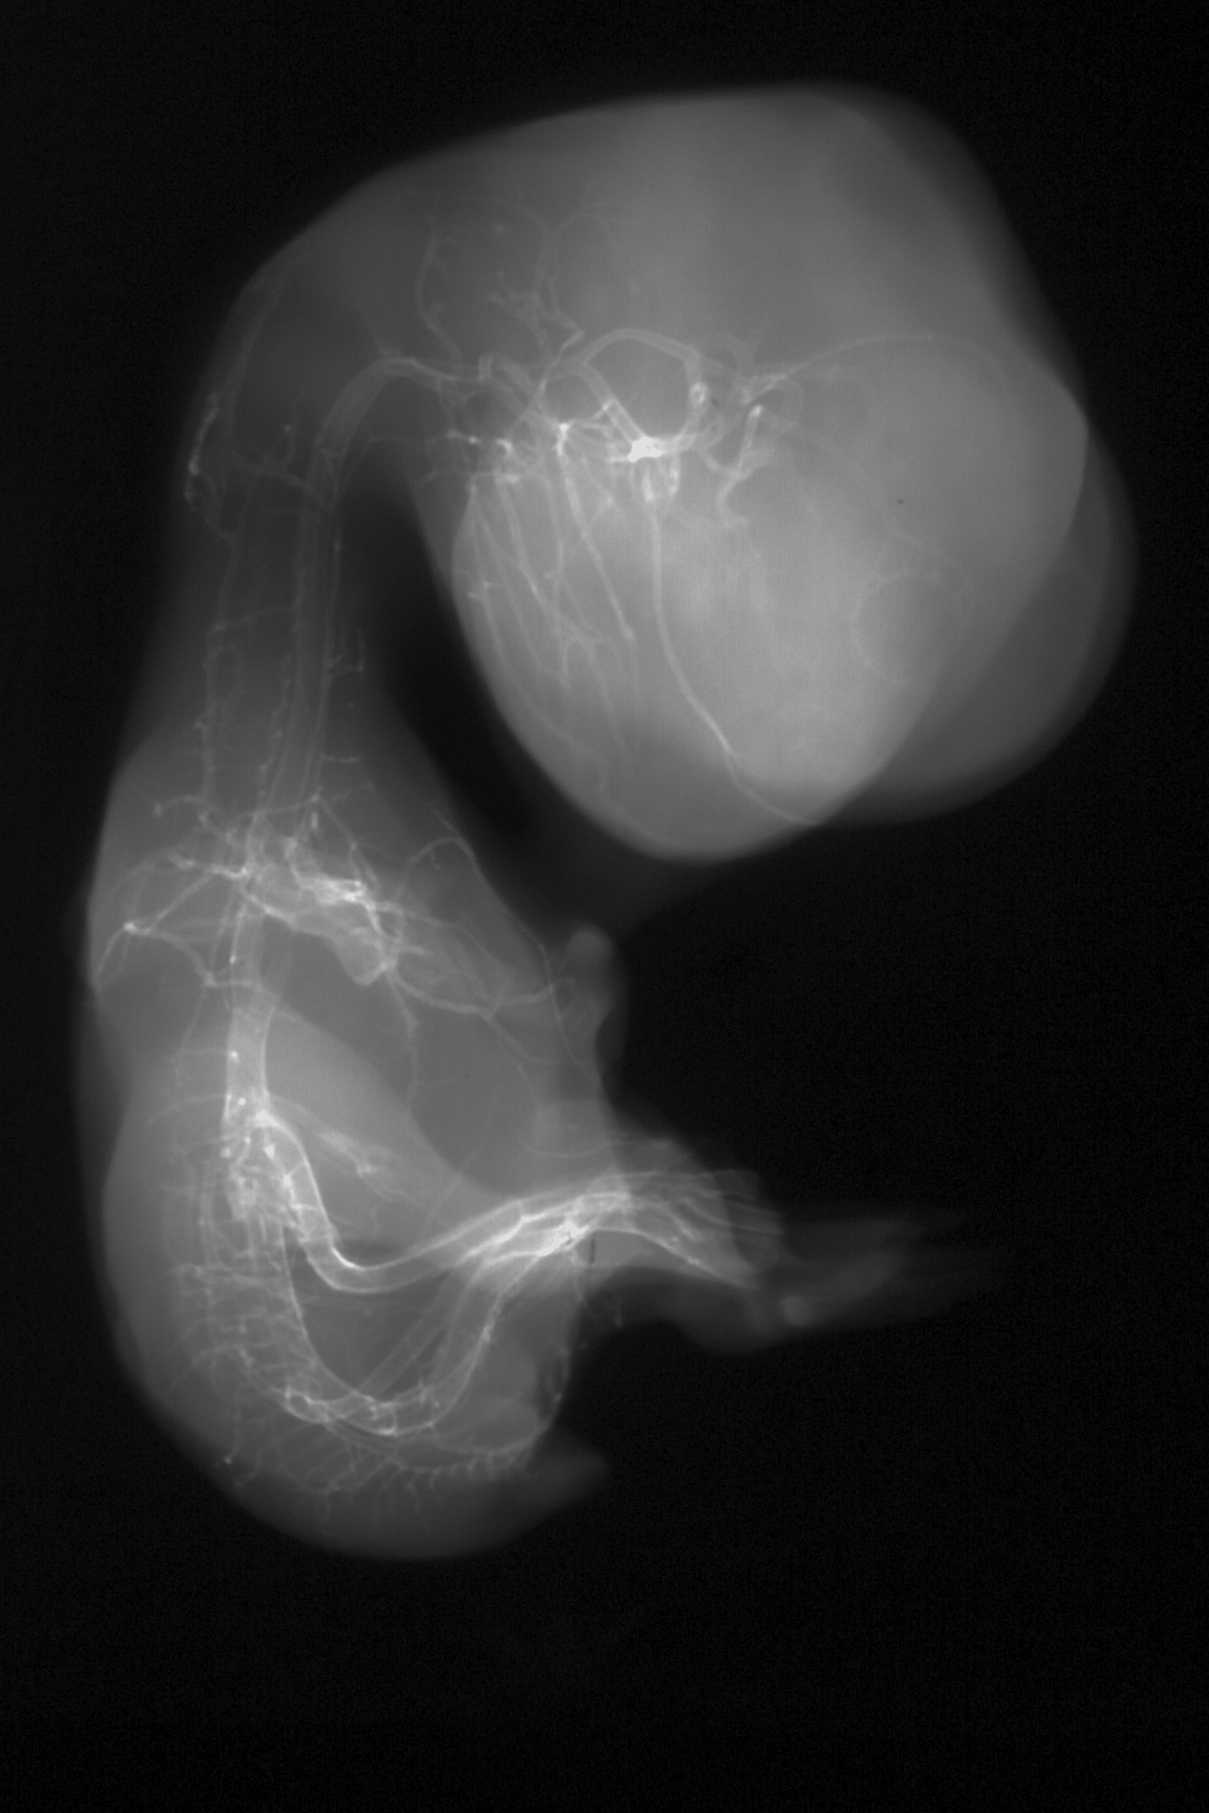

Chick Embryo Microangiography

Hamburger-Hamilton (HH) Stage 35 (approx. 8.5 - 9 days)

X-Ray Micrographs